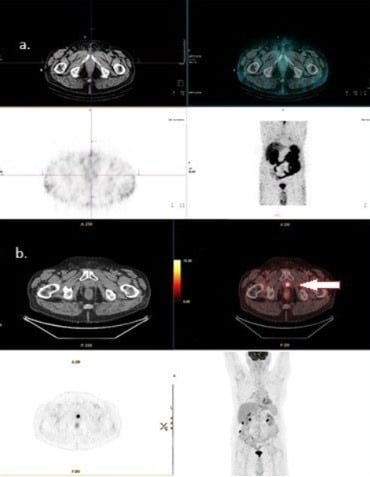

Emerging PET Imaging Agents and Targeted Radioligand Therapy: A Review of Clinical Applications and Trials

Targeted radioligand therapy (RLT) is an emerging field in anticancer therapeutics with great potential across tumor types and stages of disease. While much progress has focused on agents targeting somatostatin receptors and prostate-specific membrane antigen (PSMA), the same advanced radioconjugation methods and molecular targeting have spurred the development of numerous theranostic combinations for other targets. A number of the most promising agents have progressed to clinical trials and are poised to change the landscape of positron emission tomography (PET) imaging. Here, we present recent data on some of the most important emerging molecular targeted agents with their exemplar clinical images, including agents targeting fibroblast activation protein (FAP), hypoxia markers, gastrin-releasing peptide receptors (GRPrs), and integrins. These radiopharmaceuticals share the promising characteristic of being able to image multiple types of cancer. Early clinical trials have already demonstrated superiority to 18F-fluorodeoxyglucose (18F-FDG) for some, suggesting the potential to supplant this longstanding PET radiotracer. Here, we provide a primer for practicing radiologists, particularly nuclear medicine clinicians, to understand novel PET imaging agents and their clinical applications, as well as the availability of companion targeted radiotherapeutics, the status of their regulatory approval, the potential challenges associated with their use, and the future opportunities and perspectives. Full article

Show Figures

Figure 1